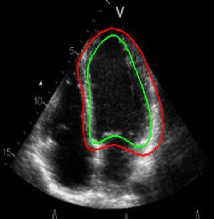

Refer to captionRefer to captionRefer to captionRefer to captionRefer to captionRefer to captionRefer to captionRefer to captionRefer to captionRefer to captionRefer to captionRefer to caption\begin{array}[]{cc}\includegraphics[width=112.0187pt]{lv-2-init.pdf}&\includegraphics[width=112.0187pt]{lv-2.pdf}\\ \includegraphics[width=112.0187pt]{lv-3-init.pdf}&\includegraphics[width=112.0187pt]{lv-3.pdf}\\ \includegraphics[width=112.0187pt]{lv-1-init.pdf}&\includegraphics[width=112.0187pt]{lv-1.pdf}\\ \end{array}

Figure 15: Segmentation of left ventricle wall of the heart in an MR image taken from [42]. Left column shows initialization and right column shows converged result.

5.5 Ring templates

We next develop templates for objects with hole(s) in their structure. These templates are called ring templates. Figures 15 and 16 show examples of ring templates. The area enclosed between the red contours act as region 1subscript1\Re_{1} and the area between the green contours is region 0subscript0\Re_{0}. Figure 17 shows the construction of the ring contours. The two seemingly unconnected contours are actually one connected contour. Hence, partial derivative calculations in equation (26) are still valid.

In Figure 15, the ring template has been used for segmenting the left ventricular (LV) wall of heart in cardiac MR images. Another example is shown in Figure 16. The template used in both examples has a greater thickness in the inner ring-shaped annular region than the outer annular region. This was done to facilitate obtaining the desired object’s structural information by means of the contrast (for example, between the endocardium and the LV wall) that a good initialization can offer. Hence, while designing a template, we can incorporate prior knowledge of the object and its surroundings.